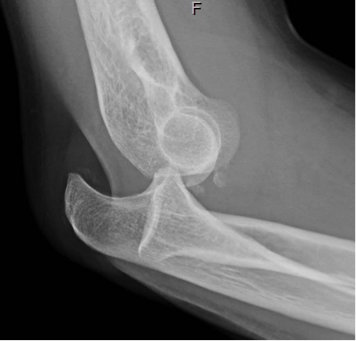

“Simple” Elbow Dislocation

The Case: 44-year-old man with a fall presents with right elbow pain. On examination, the elbow is held at 45 degrees flexion with posterior prominence of the olecranon. The extremity is neurovascularly intact. A radiograph obtained reveals a posterior elbow dislocation which is reduced with procedural sedation.

Why it Matters: A simple posterior elbow dislocation is one without concomitant fractures (other than small periarticular avulsions 1-2 mm in diameter). While complex elbow dislocations (large intra-articular fractures, most commonly of the radial head and/or coronoid process) frequently require surgery due to significant soft tissue injury and joint instability, simple elbow dislocations are reduced in the emergency department with procedural sedation. Just like any extremity injury requiring a reduction, a documented neurovascular exam before and after the procedure is performed. This is particularly important for elbow dislocation as there are several important neurovascular structures in close proximity. Watch out for injuries to the brachial artery (rare, but often subtle), ulnar, or median nerve.